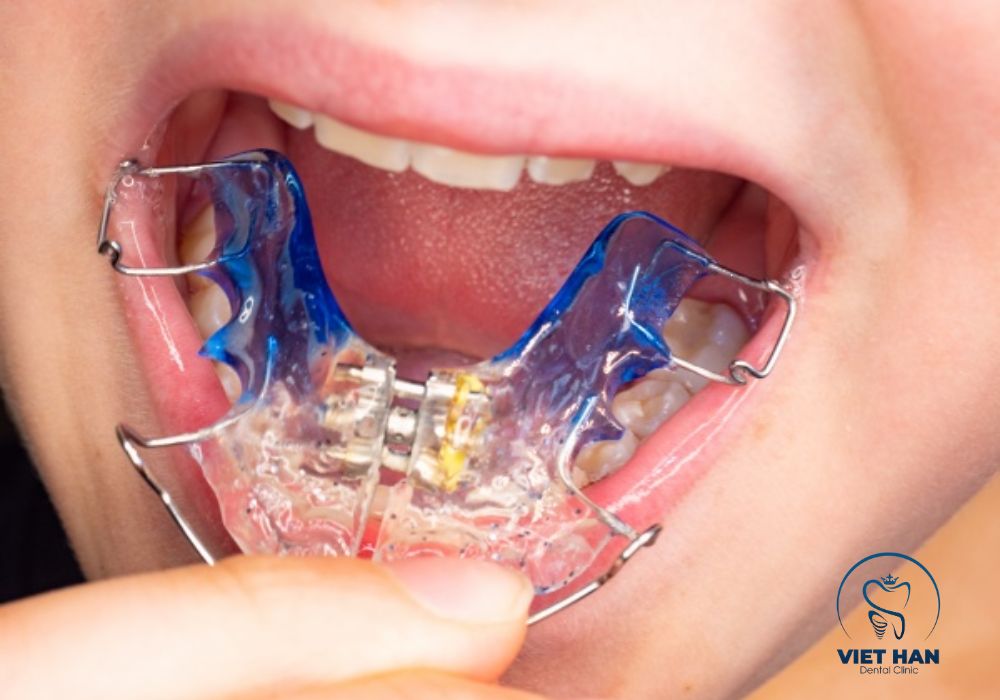

Một số phương pháp nong hàm phổ biến gồm:

• Bằng dây cung: phù hợp trường hợp nhẹ

• Nong hàm nhanh (RPE): mở rộng xương hàm nhanh chóng

• Nong hàm chậm: lực nhẹ, ổn định, ít đau

Ngoài ra, khí cụ nong hàm có thể là loại tháo lắp hoặc cố định. Việc lựa chọn phương pháp sẽ do bác sĩ quyết định dựa trên tình trạng cụ thể.